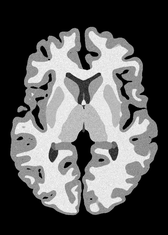

4.2 Registration to a 100 micron ex-vivo brain MRI volume

To showcase the efficacy of our method on real large scale images, we register a 250 in-vivo MRI image (Lüsebrink et al., 2017) to a 100 ex-vivo FLASH human brain volume (Edlow et al., 2019). This represents an inverse problem with more than 11.2B optimizable parameters (compared to 20M for clinical datasets), or 44.8GB of GPU memory. The entire problem does not fit on most GPUs, necessitating distributed multimodal registration. We optimize a composite transform - affine followed by a diffeomorphic mapping; details can be found in Section E.1. Multimodal deformable registration took 58 seconds on 8 NVIDIA A6000 GPUs, which is unprecedented at this resolution. Fig. 6 shows qualitative results, highlighting the ability to register highly detailed structures such as cerebellar white matter; these structures are not visible at macroscopic scales. The resultant advantages of performing registration at this scale can allow researchers to characterize the neuroanatomy at microscopic resolutions and allow morphometric analysis of cortical layers and subcortical nuclei among other structures.